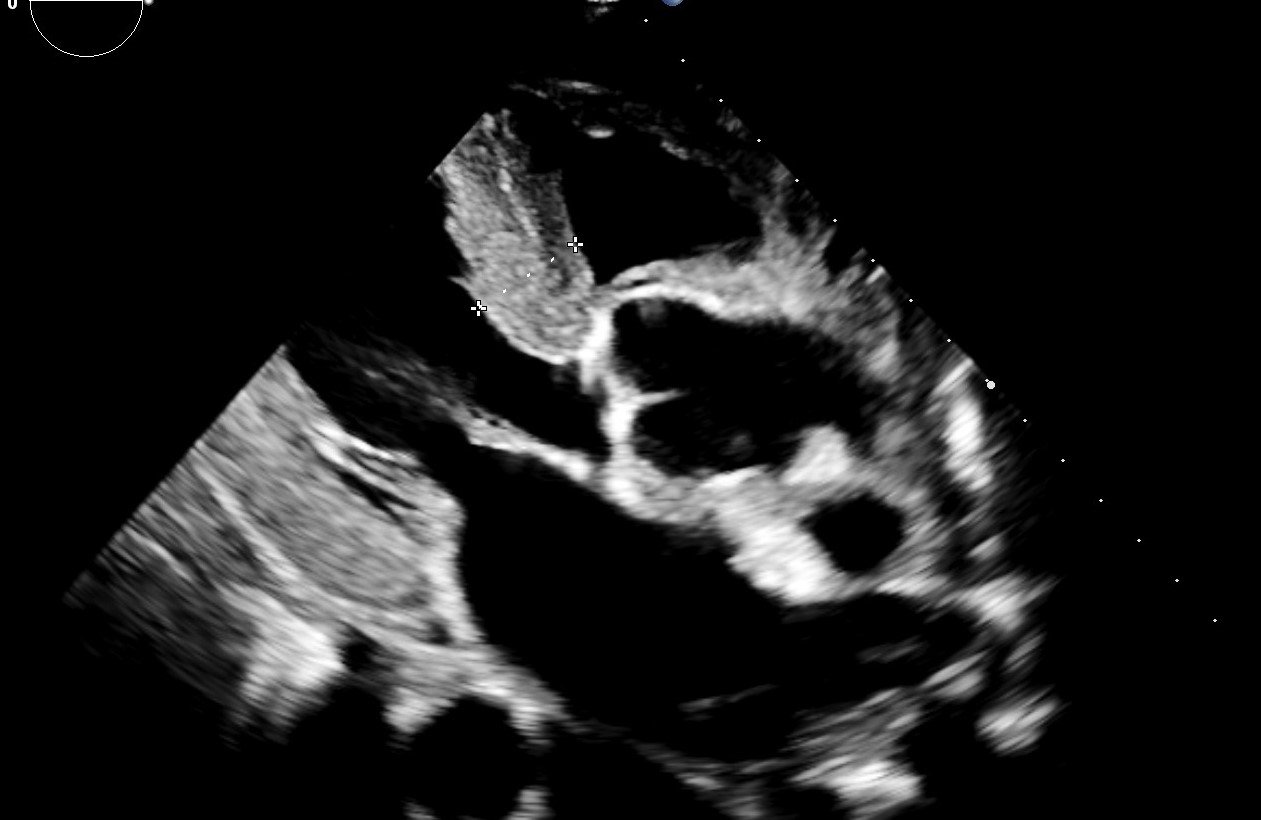

Helios ECHO-Akademie

Seit mehr als 20 Jahren führen wir Echokardiographiekurse durch. Kooperationspartner waren bisher der Bund Deutscher Internisten und die Deutsche Gesellschaft für Kardiologie. In Kooperation mit der Helios-Arbeitsgruppe „kardiale Bildgebung“ werden die Kurse jetzt durch die Helios-ECHO-Akademie an den Helios Dr. Horst Schmidt Kliniken Wiesbaden angeboten.

Die praktischen Übungen setzen sich aus Echokardiographieren in kleinen Gruppen, in Abhängigkeit vom Kenntnisstand auch am Patienten, Patientendemonstrationen und Fallbesprechungen mit eigener Befundung und Erlernen der Befunderhebung zusammen.

Unser langjährig stabiles und sehr erfahrenes Team besteht aus klinisch tätigen Kardiologen mit besonderer echokardiographischer Expertise, die ein höchstes Maß an echokardiographischer Qualität gewährleisten. Die Vermittlung einer klinisch relevanten Echokardiographie steht ganz im Vordergrund unserer Kurse. Eine kritische Auseinandersetzung erfolgt ebenso mit der Methode „Echokardiographie“.